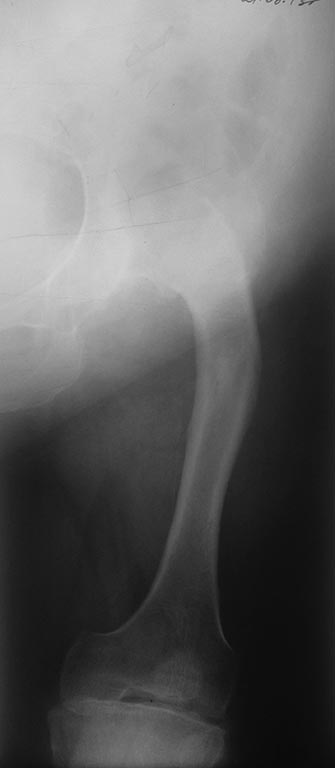

левого бедра (Crowe IV)/Гонартроз слева III. Варусные деформации обоих

коррекцией варусной деформации. Вторым этапом

эндопротезирование слева с укорачивающая и корригирующей остеотомией.